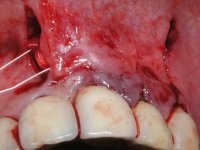

I have decided to replace the old fixed partial dentures to improve aesthetics and simultaneously eliminate root exposures. In order to do so, periodontal plastic surgery – tunneling procedure - was a priority, to increase the thickness of the soft-tissue and to do a coronal repositioning to reduce the root exposures.

PERIODONTAL PLASTIC SURGERY:

Dr. Manuel Neves, Clínica Dr. Manuel Neves.